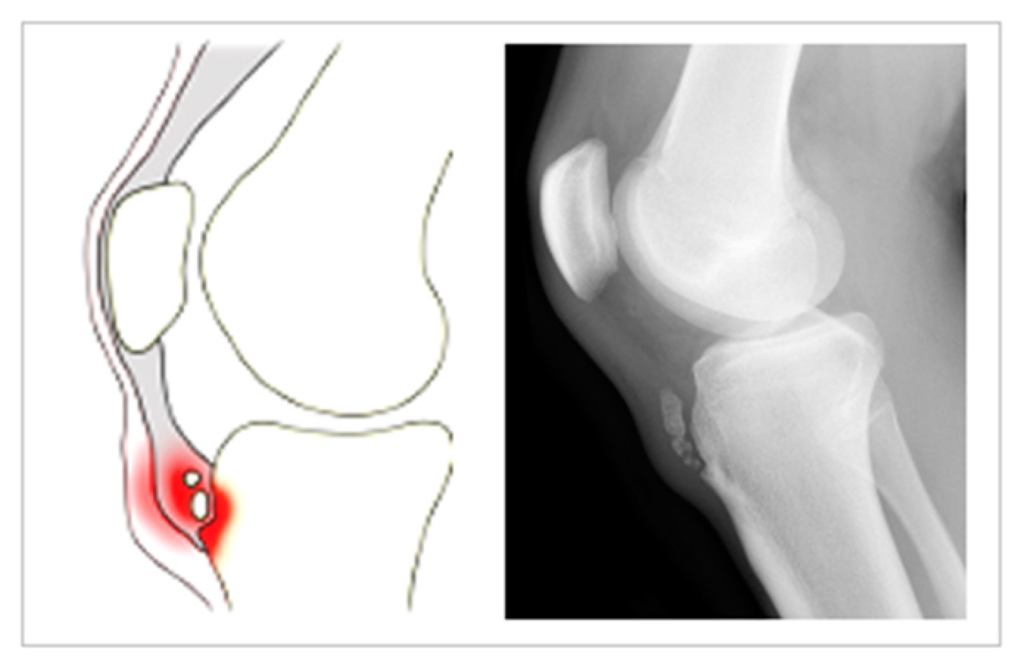

Osgood-Schlatter Disease